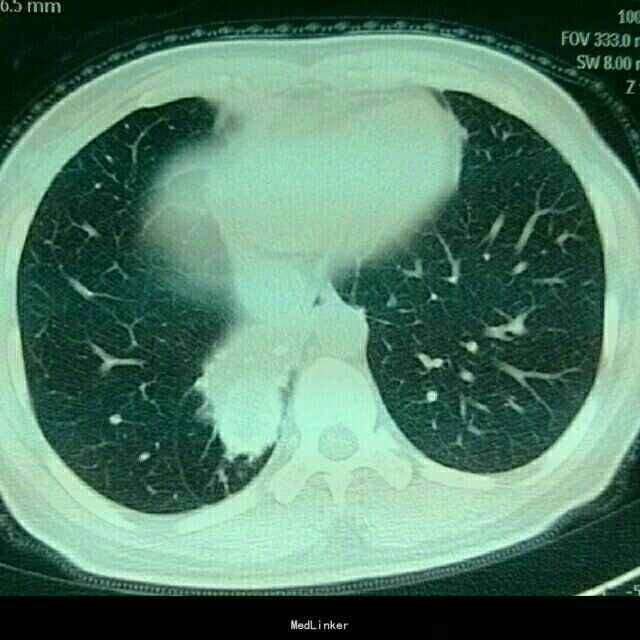

患者为43岁女性,因“咳嗽咳痰伴胸闷、气紧4+月”入院。患者4+月前无明显诱因出现咳嗽咳痰,伴胸闷气紧,外院行相关检查后诊断为“肺炎”,予抗感染治疗20天后无明显缓解。遂于我院就诊。

查体:双侧锁骨上淋巴结未触及肿大。视:双侧胸廓对称,未见畸形,双肺呼吸动度对称。触:触觉语颤对称,未触及胸膜摩擦感,心尖搏动位于左锁骨中线,未见异常搏动。叩:双肺叩清音,双肺活动度对称。听:右下肺肺呼吸音低,未闻及干湿罗音及胸膜摩擦音,心前区未及病理性杂音。我院胸部CT示:右肺下叶不规则片团影,伴右肺下叶不张。

术前诊断为右下肺结核球。于全麻下行右肺下叶切除术。术中取出病灶,可见干酪样坏死。术后病理确诊为肺结核病灶。术后患者恢复可,仍需抗痨治疗。